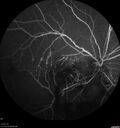

Branch Retinal Vein Occlusion - Both Eyes - Edema OD and NVE OS - Severe Non-perfusion Both Eyes369 views83 year old man with vision loss for 3 months not sure which eye. VA 20/100 OD and 20/50 OS. Tried avastin once without much improvement in the right eye and then lost to follow-up. FA in the left eye shows leaking NVENov 30, 2020

|

Branch Retinal Vein Occlusion - Both Eyes - Edema OD and NVE OS - Severe Non-perfusion Both Eyes347 views83 year old man with vision loss for 3 months not sure which eye. VA 20/100 OD and 20/50 OS. Tried avastin once without much improvement in the right eye and then lost to follow-up. FA in the left eye shows leaking NVENov 30, 2020